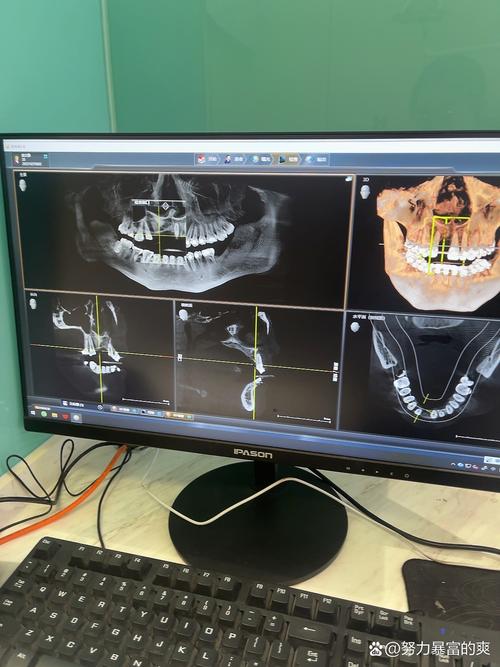

我种的牙用了三年多,从最初的忐忑不安到现在的习以为常,这段经历让我对“牙齿”有了全新的认识,缺牙那几年,我总感觉吃饭不香,连笑都小心翼翼,生怕露出牙缝里的尴尬,后来下定决心种牙,从拍CT、植入种植体到戴上牙冠,整个过程像是一场和牙齿的“重生之旅”,而如今,这颗牙早已成为我生活中不可或缺的一部分,每天陪我咀嚼美食、自信微笑。

医生还提醒我,要关注全身健康,我有轻度牙周炎,以前定期洗牙,现在洗牙时会特别告诉医生“这里有种植牙”,医生会用更温和的器械清理,避免损伤种植体,如果血糖不稳定(我是糖尿病患者),也会先控制血糖再处理牙齿问题,因为高血糖会影响骨结合,甚至导致种植体松动。